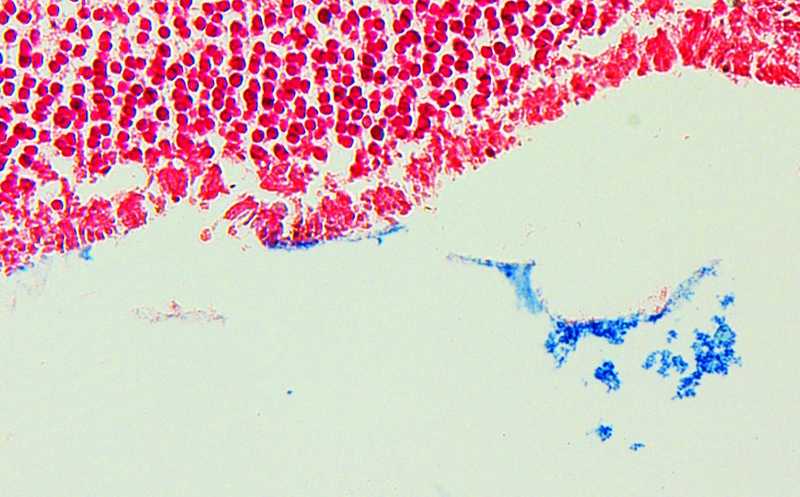

Далее ученые сравнили концентрацию железа непосредственно в сетчатке глаз, полученных в результате аутопсии от человека с глазным токсоплазмозом, вторичным по отношению к СПИДу, и от донора со здоровыми глазами. Окрашивание срезов сетчатки берлинским синим показало места накопления железа на сетчатке глаза, инфицированного токсоплазмозом, а на сетчатке нормального глаза отсутствовали участки отложения этого металла. В совокупности это показывает, что при токсоплазмозе железо из стекловидного тела перераспределяется в область сетчатки и накапливается там в больших количествах.